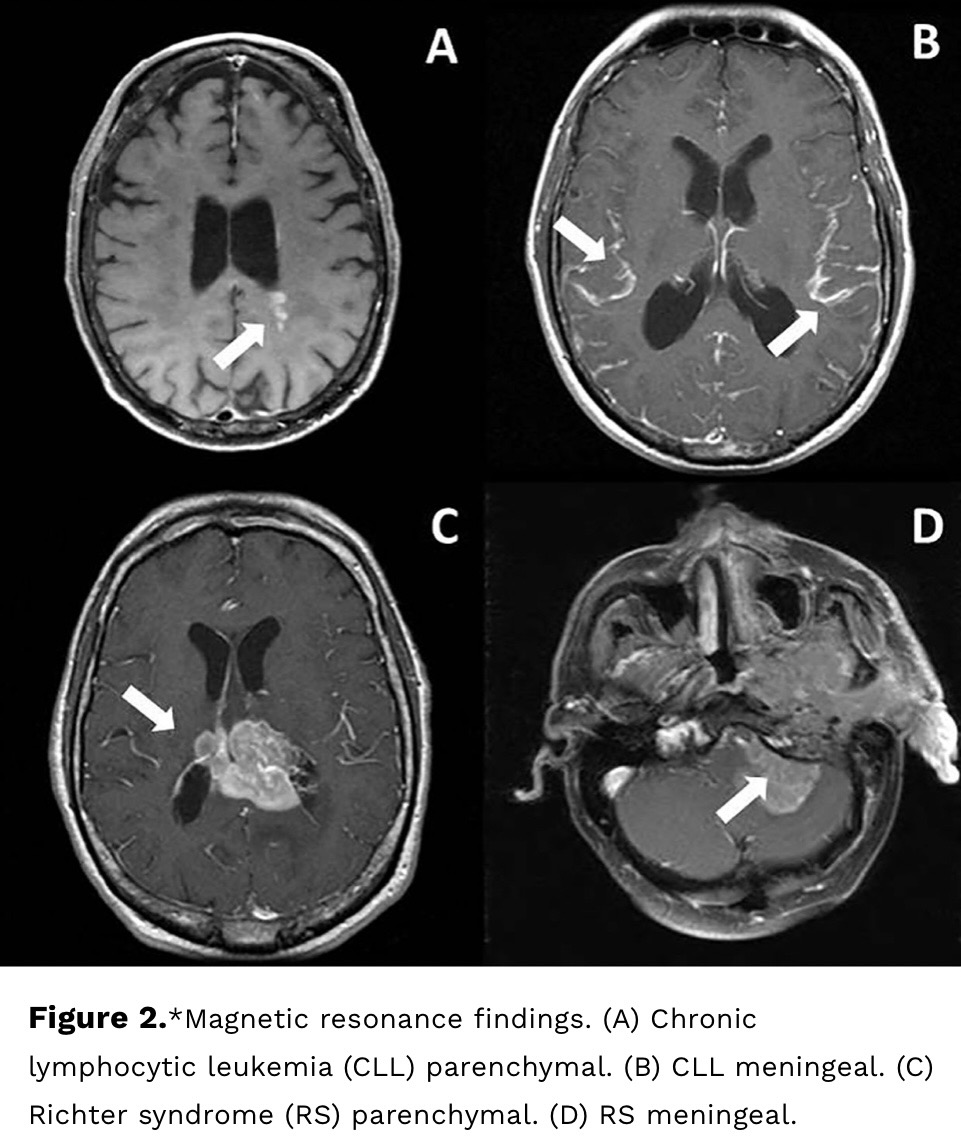

CNS Involvement in CLL